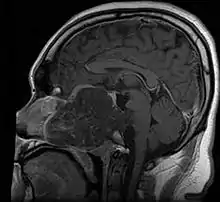

- Skull base:

- May be intracranial or extracranial, with mass effect symptoms depending on location

- Headaches and/or facial pain are common

- Pituitary insufficiency, hemianopsia/diplopia, cranial nerve deficits, nasal stuffiness.

Skull Base

- Hannover; 2007 (Germany) PMID 17695386 -- "Chordomas of the skull base: surgical management and outcome." (Samii A, J Neurosurg. 2007 Aug;107(2):319-24.)

- Retrospective. 49 patients. Transethmoidal approach 36%, pterional 23%, retrosigmoid 23%.

- Outcome: GTR 49%, subtotal resection 51%. Initial surgery GTR 78%. 5-year OS 65%, 10-year OS 39%